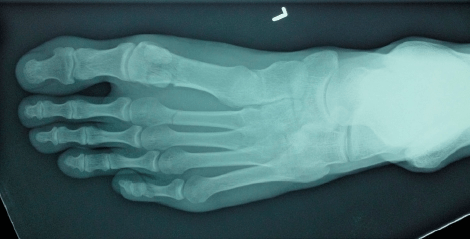

(Note: post contains X-rays of feet — I don’t know if anyone else out there has lifelong Issues with foot bones, but we thought we should give a heads-up just in case.)

Six weeks ago yesterday, I broke my foot. Suffice to say, it was a learning experience, and the main lesson was, breaking your foot is terrible, don’t do it.